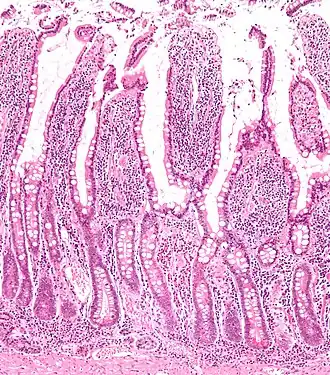

![]() Micrograph of the small intestine mucosa showing the intestinal glands - bottom 1/3 of image. H&E stain. | |

In histology, an intestinal gland (also crypt of Lieberkühn and intestinal crypt) is a gland found in between villi in the intestinal epithelial lining of the small intestine and large intestine (or colon). The glands and intestinal villi are covered by epithelium, which contains multiple types of cells: enterocytes (absorbing water and electrolytes), goblet cells (secreting mucus), enteroendocrine cells (secreting hormones), cup cells, myofibroblast, tuft cells, and at the base of the gland, Paneth cells (secreting anti-microbial peptides) and stem cells.

Structure

Intestinal glands are found in the epithelia of the small intestine, namely the duodenum, jejunum, and ileum, and in the large intestine (colon), where they are sometimes called colonic crypts. Intestinal glands of the small intestine contain a base of replicating stem cells, Paneth cells of the innate immune system, and goblet cells, which produce mucus.[1] In the colon, crypts do not have Paneth cells.[2]